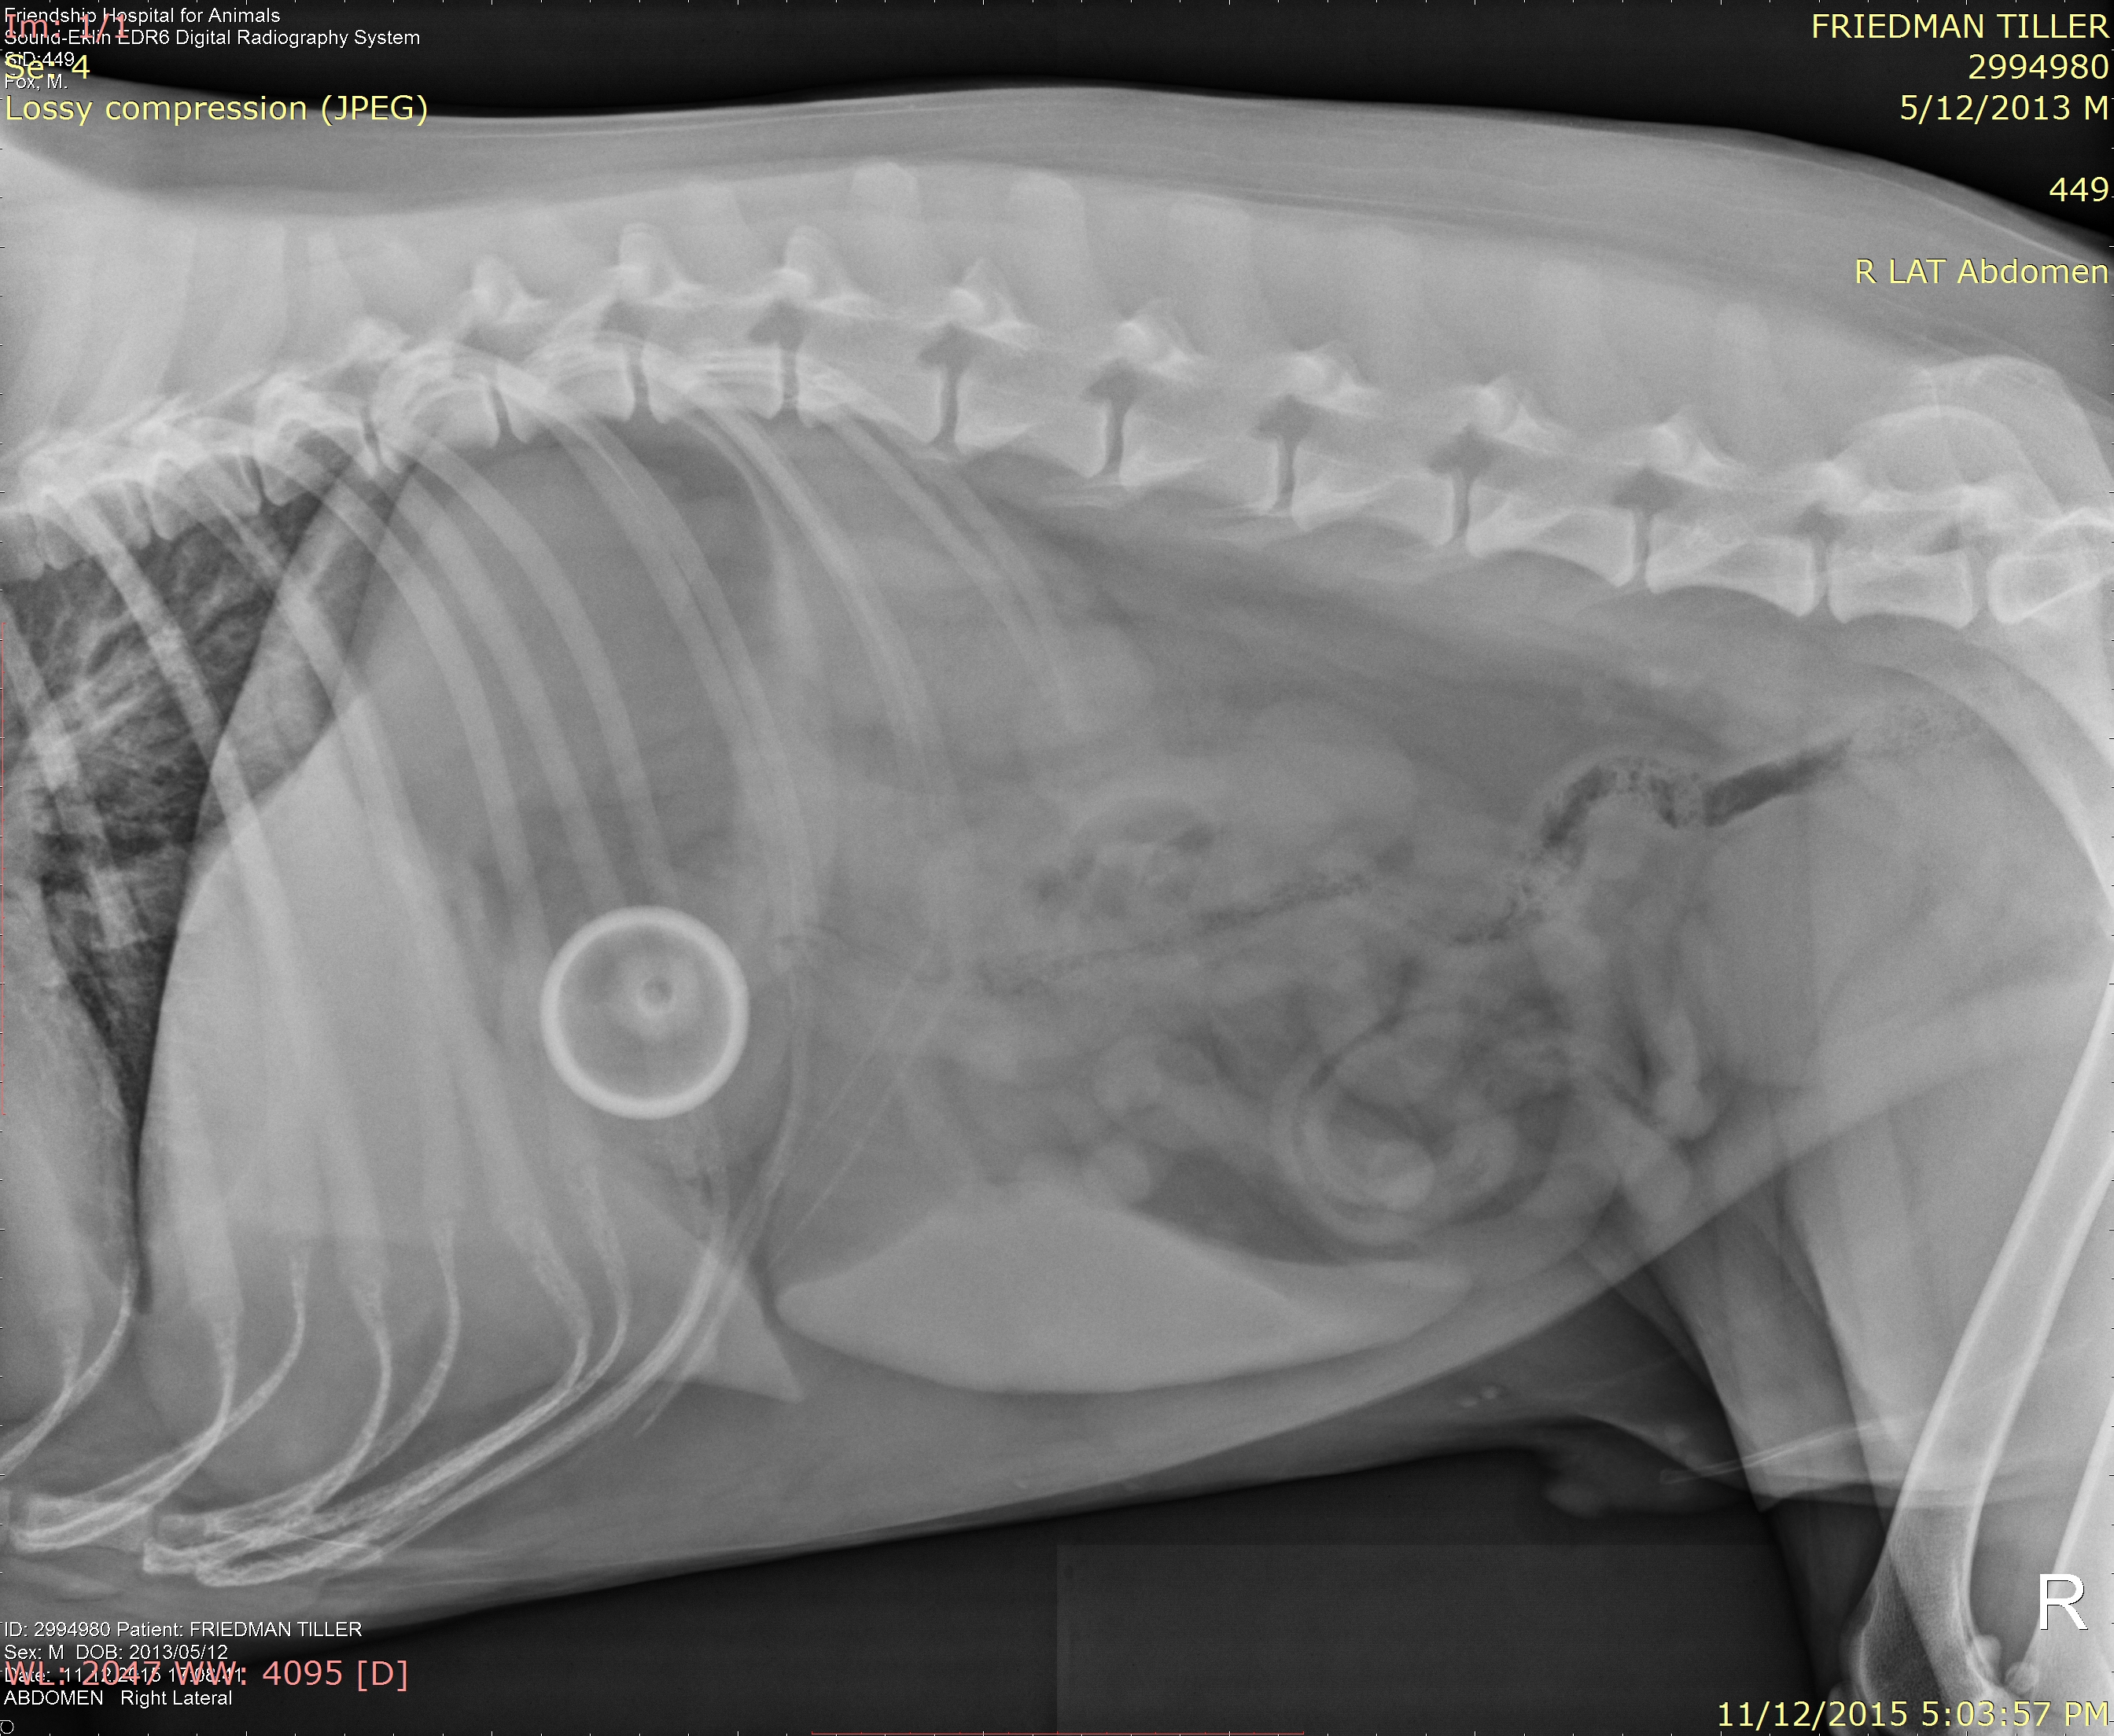

About a week ago, Tiller (who lives with my parents back in DC) got sick. He started throwing up and looked bad, so my mom took him to the vet. They took an X-ray, which showed the following:

So what is that huge circular thing in his stomach? I have had great fun showing my various residents on anesthesia this image. So far – and bear in mind these are doctors – answers have included a quarter, a ring, a golf ball, and a mini-frisbee. No one approached the size of the actual ingested object, which was this:

The quarter is for scale. My IDIOT dog somehow decided it was both possible and a good idea to swallow an entire, inflated tennis ball. What the hell!? How did that go down? How could he possibly have eaten this without anyone noticing? How does one “eat” a rubber ball at all!?